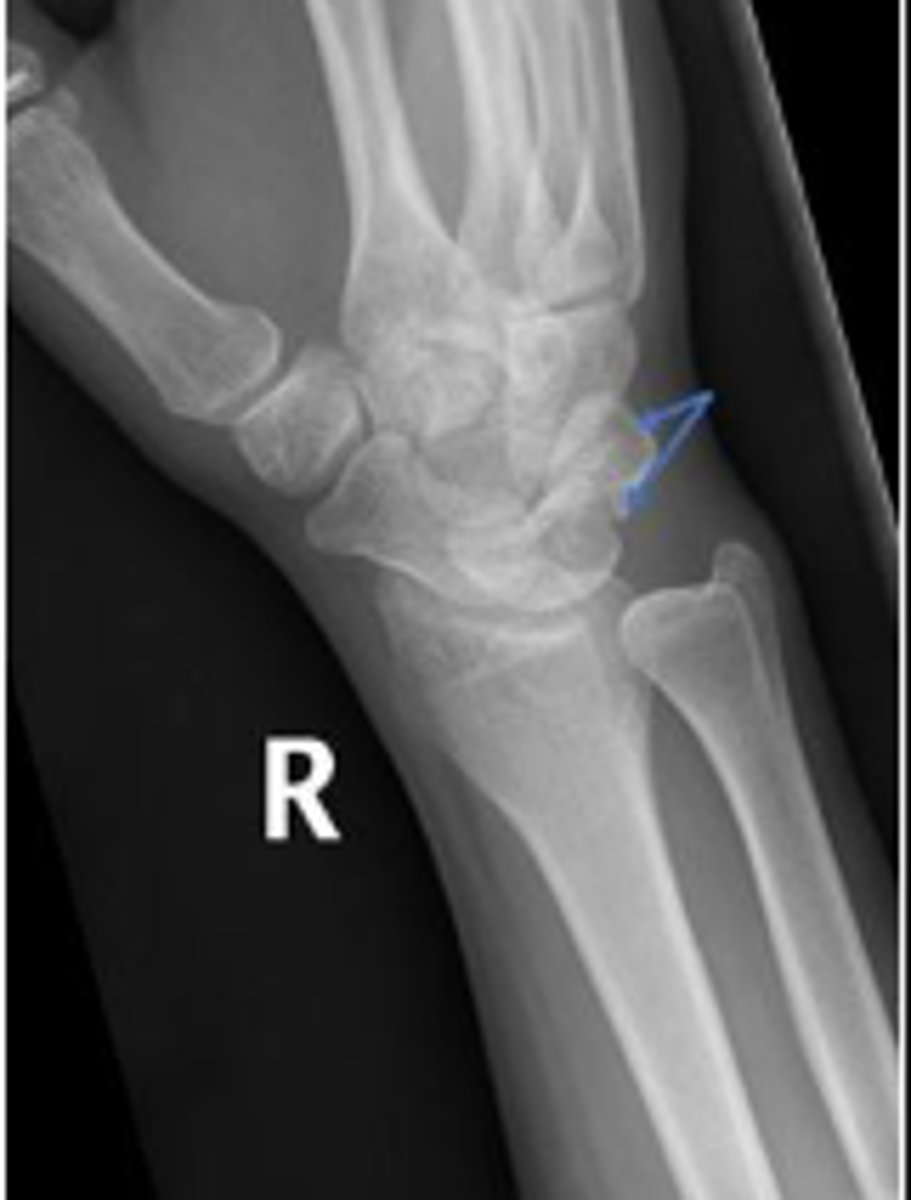

PA right wrist

What is the name of the radiographic view?

Right triquetrum

What is outlined?

Right pisiform

What is the arow pointing to?

DRUJ

What is the arrow pointing to?

What are the arrows pointing to?